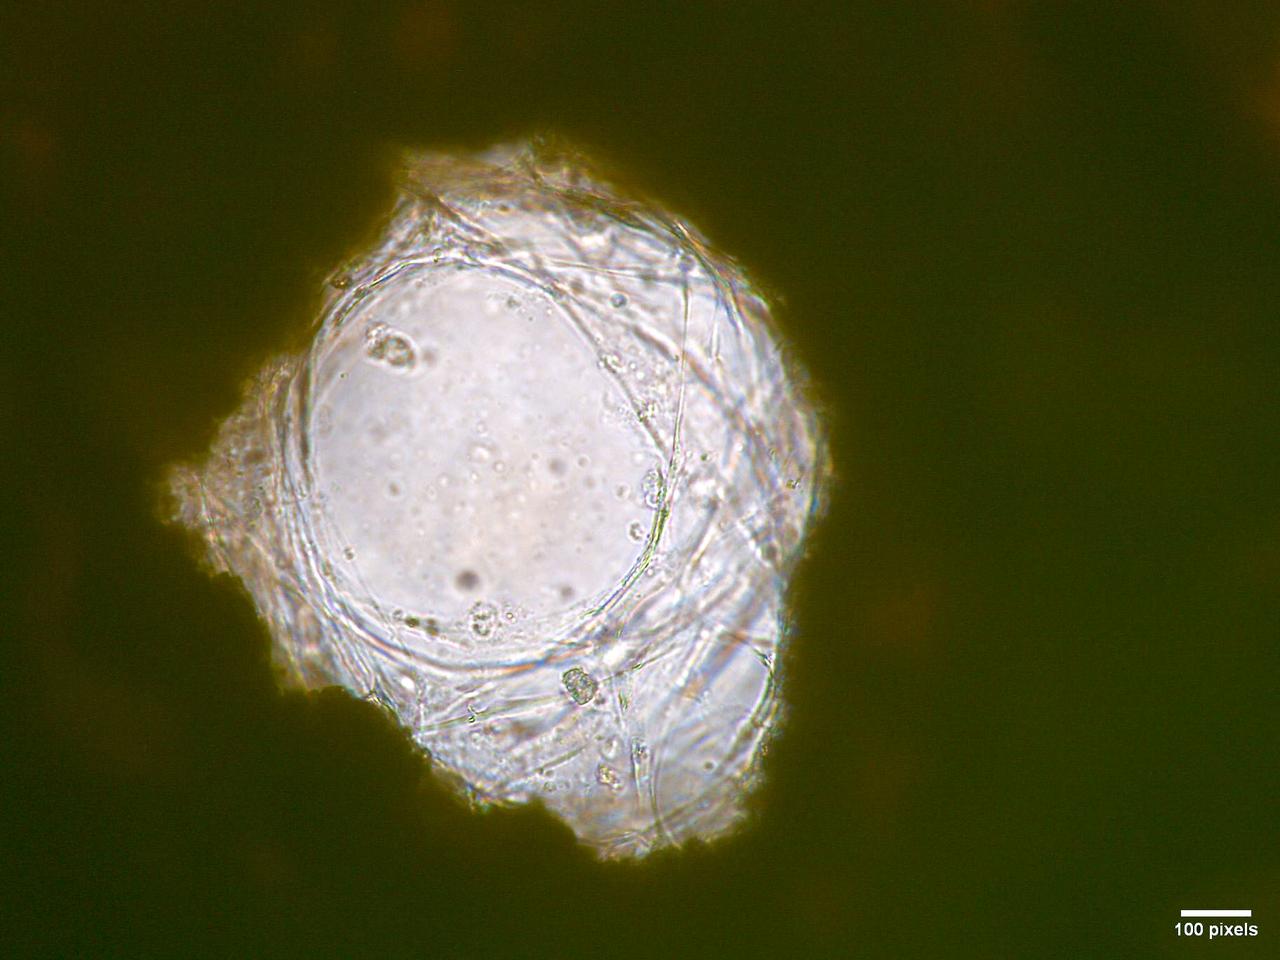

jsc2026e017237 (March 27, 2026) --- Microscopic view showing human mesenchymal stem cells (hMSCs) adhered inside one of the pores of a b.Bone scaffold as part of preflight testing for Green Bone. This investigation studies the performance of a biomimetic bone scaffold, b Bone, in microgravity aboard the International Space Station. The image highlights cellular attachment and interaction with the porous structure. A scale bar is visible in the bottom right corner, indicating 100 pixels. Credit:. DIMES Laboratory.

jsc2026e017238 (March 27, 2026) --- Microscopic view showing human mesenchymal stem cells (hMSCs) adhered inside the macropores of a b.Bone scaffold as part of preflight testing for Green Bone. This investigation studies the performance of a biomimetic bone scaffold, b Bone, in microgravity aboard the International Space Station. The image highlights cellular attachment and interaction with the porous structure. A scale bar is visible in the bottom right corner, indicating 200 pixels. Credit: DIMES Laboratory.